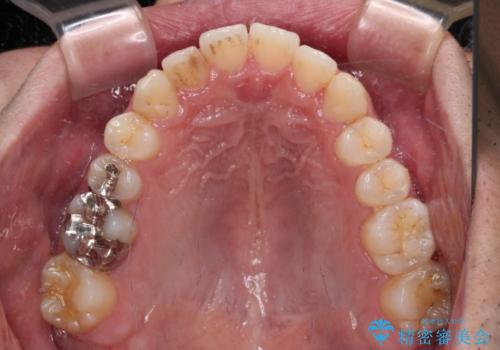

矯正治療後に銀歯をセラミックに替えたいとの要望があり、概ね歯列が整ったところで銀歯をセラミックに替え、仕上げにインビザライン1セットを使用して最終的に歯列を整えました。